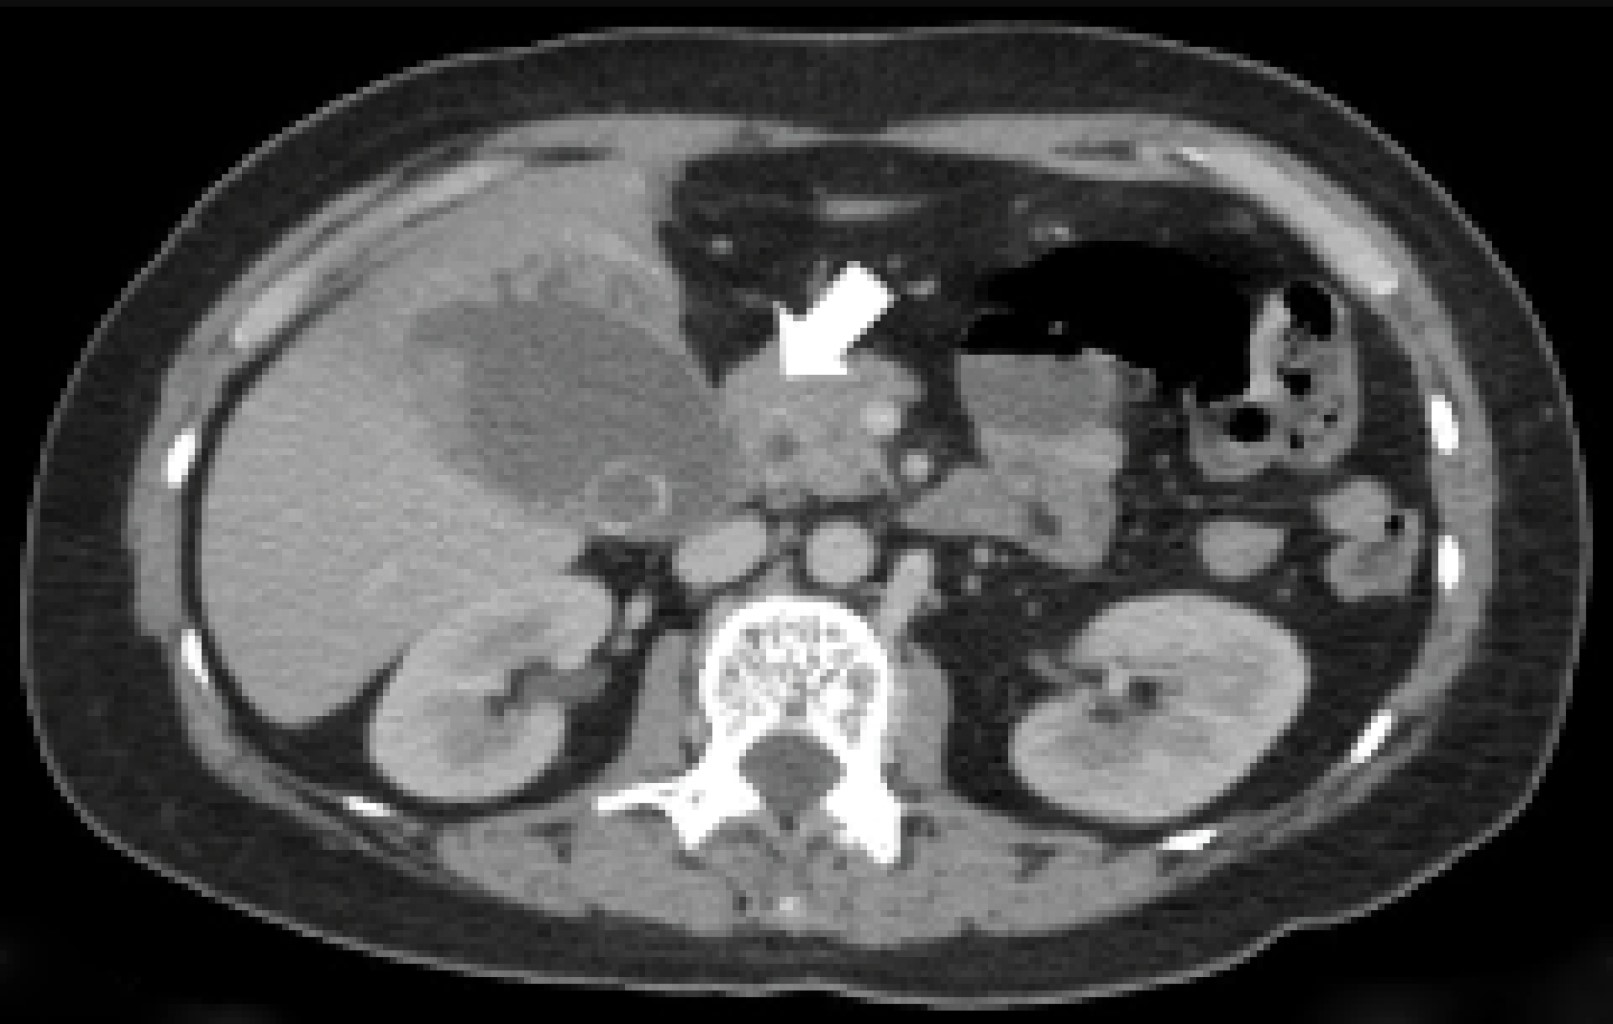

A 55-year-old female patient came to the emergency department with a picture of a month of evolution characterized by abdominal pain located in the epigastrium and right hypochondrium, radiating to the interscapular region, which was increasing, so she decided to go to the doctor who started homeopathic treatment; however, she did not improve, so she went to the emergency department of our hospital unit where the following vital signs were recorded: BP (blood pressure) 114/76 mmHg, HR (heart rate) 124 bpm, RR (respiratory rate) 16/min, and temperature of 36 °C. On questioning, the patient denied the presence of fever, nausea, vomiting, or the presence of bowel movements of decreased consistency. For her approach, general laboratories were requested, highlighting the presence of leukocytosis (12,300 mm3), elevated alkaline phosphatase, and GGT (315 and 268 U/l respectively); a CT scan of the abdomen with intravenous contrast was requested (Figures 1, 2 and 3) which showed the presence of gallbladder with impacted lithos in its interior, and an intrahepatic rupture, in addition to an intrahepatic abscess in segments IV and V (Figure 2).

Figure 2